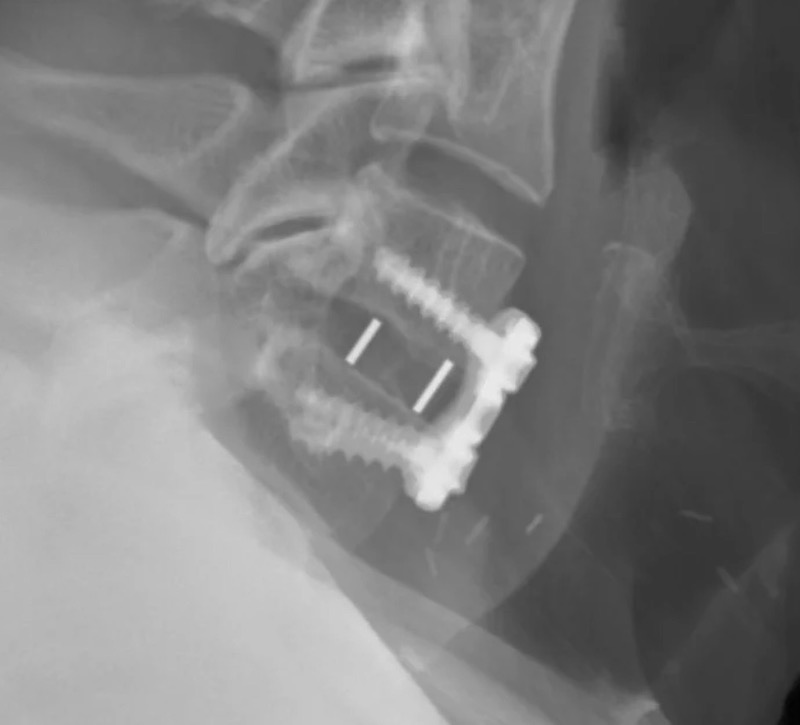

Cohere Cervical Porous PEEK ACDF Spacer

Cohere Cervical by Nuvasive (Globus) is a porous PEEK implant used for anterior cervical discectomy and fusion procedure. The porous surface structure is designed to promote bone ingrowth while maintaining the inherent biomechanical and imaging properties of PEEK.

• Radiolucent porous PEEK for bone ingrowth